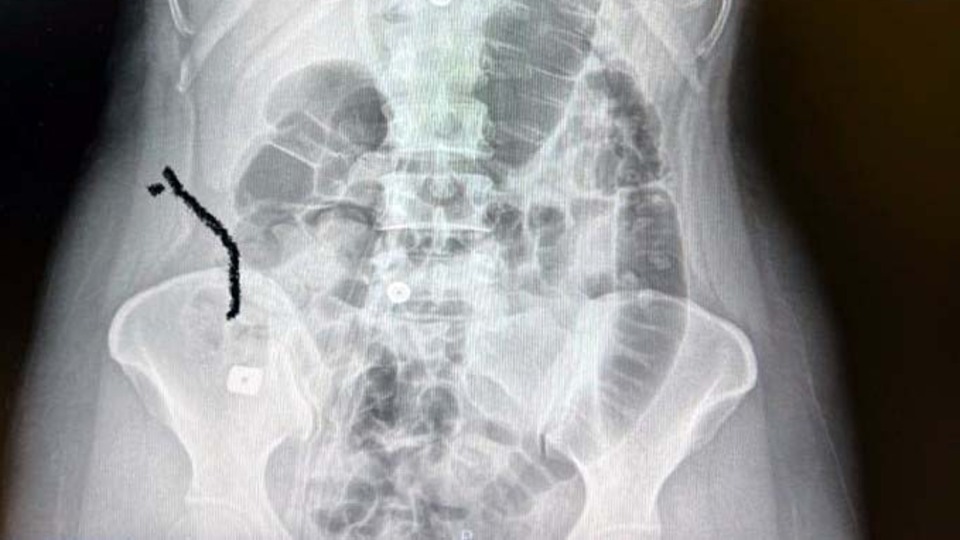

Burada yapılan kontrollerde boynuna takılan implantın yerinden oynadığı tespit edildiği için ameliyata alındı. Ameliyat sırasında implantlardan birisi çıkarılırken, diğeri tespit edilemeyince kentteki özel bir üniversitenin hastanesine sevk edildi. Burada endoskopi yapılan Tıraş'ın yemek borusunda yırtık olduğu, implantın da midesinde bulunduğu tespit edildi. Yoğun bakım ünitesine alınan Sultan Tıraş, yapılan hazırlıkların ardından ameliyata alındı. Tıraş, riskli olarak değerlendirilen ameliyatının başarılı geçmesiyle sağlığına kavuştu.

Ameliyatı gerçekleştiren Prof. Dr. Levent Elbeyli, Sultan Tıraş´ın hastaneye getirildiğinde bilincinin kapalı olduğunu ve hayatını kaybetme riskinin çok yüksek olduğunu söyledi. Yaşanan bu olayın tıp literatüründe görülmediğini belirten Elbeyli, yapılan radyolojik tetkikler ve değerlendirmeler sonucu daha önce başka bir merkezde boyun omurlarına yerleştirilen metal disklerin yerinden oynadığını ve birisinin de midede olduğunun tespit edildiğini kaydetti.

Yapılan endoskopide yemek borusunda bir delinme olduğunu tespit ettiklerini anlatan Elbeyli, riskli bir ameliyat gerçekleştirdiklerini belirterek, orada iğne ucu kadar bile açık nokta bırakma şanslarının olmadığını dile getirdi ve şunları söyledi: "Bu hastamıza iki adet implant takılmış ve zaman içinde yerinden oynayarak yemek ve nefes borusunda bir sıkıntı yaratmış. Daha sora çekilen MR ve radyolojik tetkiklerle belirleniyor. Semptomların iyice artması karşısında hastamız bize yönlendiriliyor. Yaptığımız incelemelerde bu implantların yerinden oynadığı ve bir şekilde yer değiştirdiğini gördük. Bu alan komplike bir alan. Yapılan endoskopide yemek borusunda bir delinme olduğunu tespit ettik. Devamında midede bu implantların birinin görünmesi söz konusu. Diğer implantın da yerinden oynadığını görüyoruz. Böyle bir durumda hayati tehlikesi son derece yüksek. Yemek borusu kontamine bir alan. Hastayı direkt yoğun bakıma aldık. Bu kritik tablonun tedavi sürecini başlattık. Hayati tehlikenin yüksek olduğunu da hasta yakınlarıyla görüşüp bilgilendirdik. Ameliyatla yemek borusuna kaçan ve hatta nefes borusunda da tahrip olmuş olabileceği bilgisini ve birkaç aşamada cerrahi işlem gerektiğini belirttik. Ameliyat, göğüs boşluğu ve boyun bölgesinden delinmenin olduğu yerin ameliyatla görülmesi ve tedavinin yapılmasıydı. 6 saati geçen bir ameliyat sürecimiz oldu. Hastanın boyun kısmından yaklaşık yarım litre iltihabi ve prülan ve gıda artıkları olan cerahat atığı temizlendi. Uzun süre kaçak nokta temizlendi ve tedavi edildi. Orada iğne ucu kadar bile açık bırakma şansınız yoktur. Ameliyatı başarıyla tamamladık. 3 gün yoğun bakımdan sonra sağlığına kavuştu. Ameliyattan sonra daha birtakım risklerin olabileceğini anlattık. Yoğun bakımın ardından hastamıza 10 gün kadar da serviste tedavi uyguladık. Bunun ardından hastamızı normal beslenir ve hayatını normal şekline koyacak hale geldikten sonra evine yolcu ettik. Bugün çok sağlıklı ve aramızda."